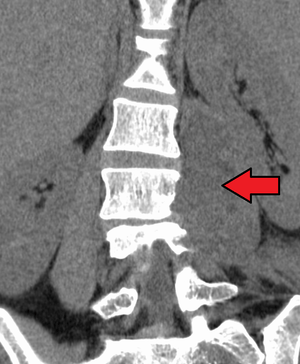

An abscess in the psoas muscle of the abdomen may be caused by lumbar tuberculosis. Owing to the proximal attachments of the iliopsoas, such an abscess may drain inferiorly into the upper medial thigh and present as a swelling in the region.

Paraspinal abscess in the psoas muscle